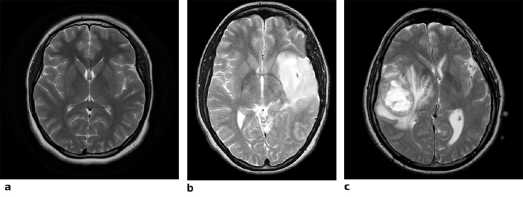

Pertumbuhan sel yang tidak normal dan tidak terkendali pada otak merupakan penyebab tumor otak. Jenis tumor otak yang paling umum ditemukan adalah Glioma yang memiliki tingkat kematian yang tinggi. Glioma dibagi menjadi dua jenis, yaitu High Grade Glioma (HGG) dan Low Grade Glioma (LGG). Umumnya, pasien yang menderita HGG memiliki harapan hidup yang lebih rendah dibandingkan dengan LGG. Biasanya, pasien yang menderita LGG memiliki harapan hidup antara 6 sampai 15 tahun, namun pasien yang menderita HGG hanya memiliki harapan hidup sekitar 15 bulan [22].

Gambar 1: (a) Otak Normal, (b) Low Grade Glioma, (c) High Grade Glioma